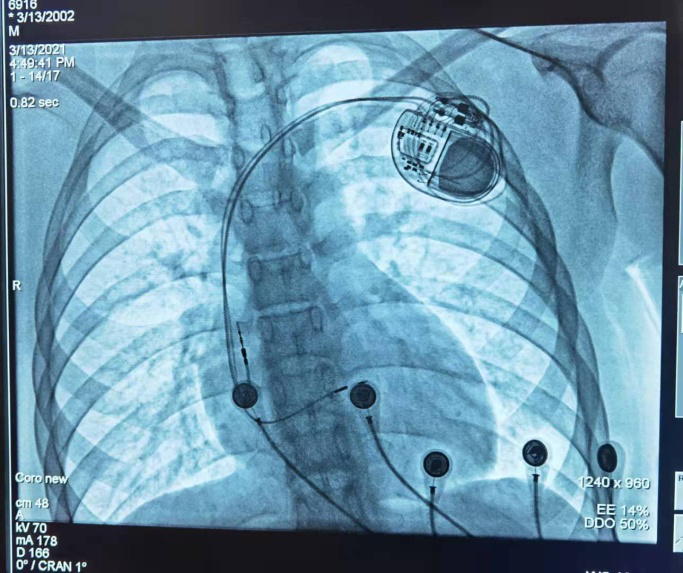

患者植入心脏起搏器图

接着,做好充足的术前准备后,在主刀心血管内科韦颖副主任医师和医护团队的高效配合下,经过1个小时40分钟的手术,顺利为小浩植入桂西北首例3.0T MRI兼容起搏器。术后小浩感觉良好,心率也从术前的每分钟30-40次恢复到了正常水平。